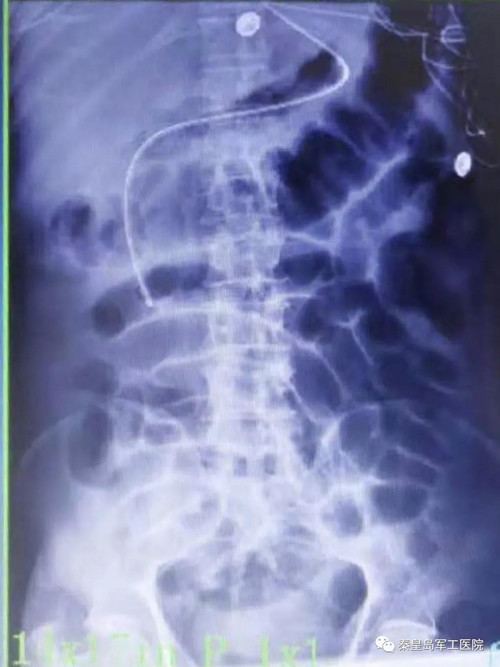

为提高危重症患者置管成功率,王秋艳主任与姚明慧护士长配合,通过床旁超声引导下成功进行鼻肠管的置入。床旁超声被喻为看得见的“听诊器”,在重症医学科的应用日益广泛。该技术利用超声优势,在床旁进行实时引导,准确通过幽门后进行肠内置管。

传统的鼻肠管置入多采用盲插或在介入、x线、胃镜引导下实施,x线及介入引导置管需转运患者,流程相对繁琐。胃镜及介入引导下置管成功率高,但操作需专业人员进行。

相比传统方法,超声引导更加安全稳定,无副作用,置管成功率高。通过超声评估胃排空功能,测量胃残余量等优势,可以尽快给足营养支持,更好的保证患者安全,有效节省人力资源。